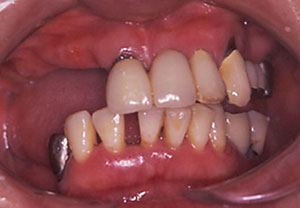

初診時

【症例1 57歳 女性 上顎前歯の違和感】

| 治療内容 | 主訴:上顎の前歯部分が疼痛により当院へ相談しに来院されました。 処置:骨が欠損していた難症例でしたので、帆年再生療法(GBR)と歯肉移植を併用したインプラント治療を行いました。十分な骨の再生が得られ、きれいな歯が入ったと喜ばれました。 |